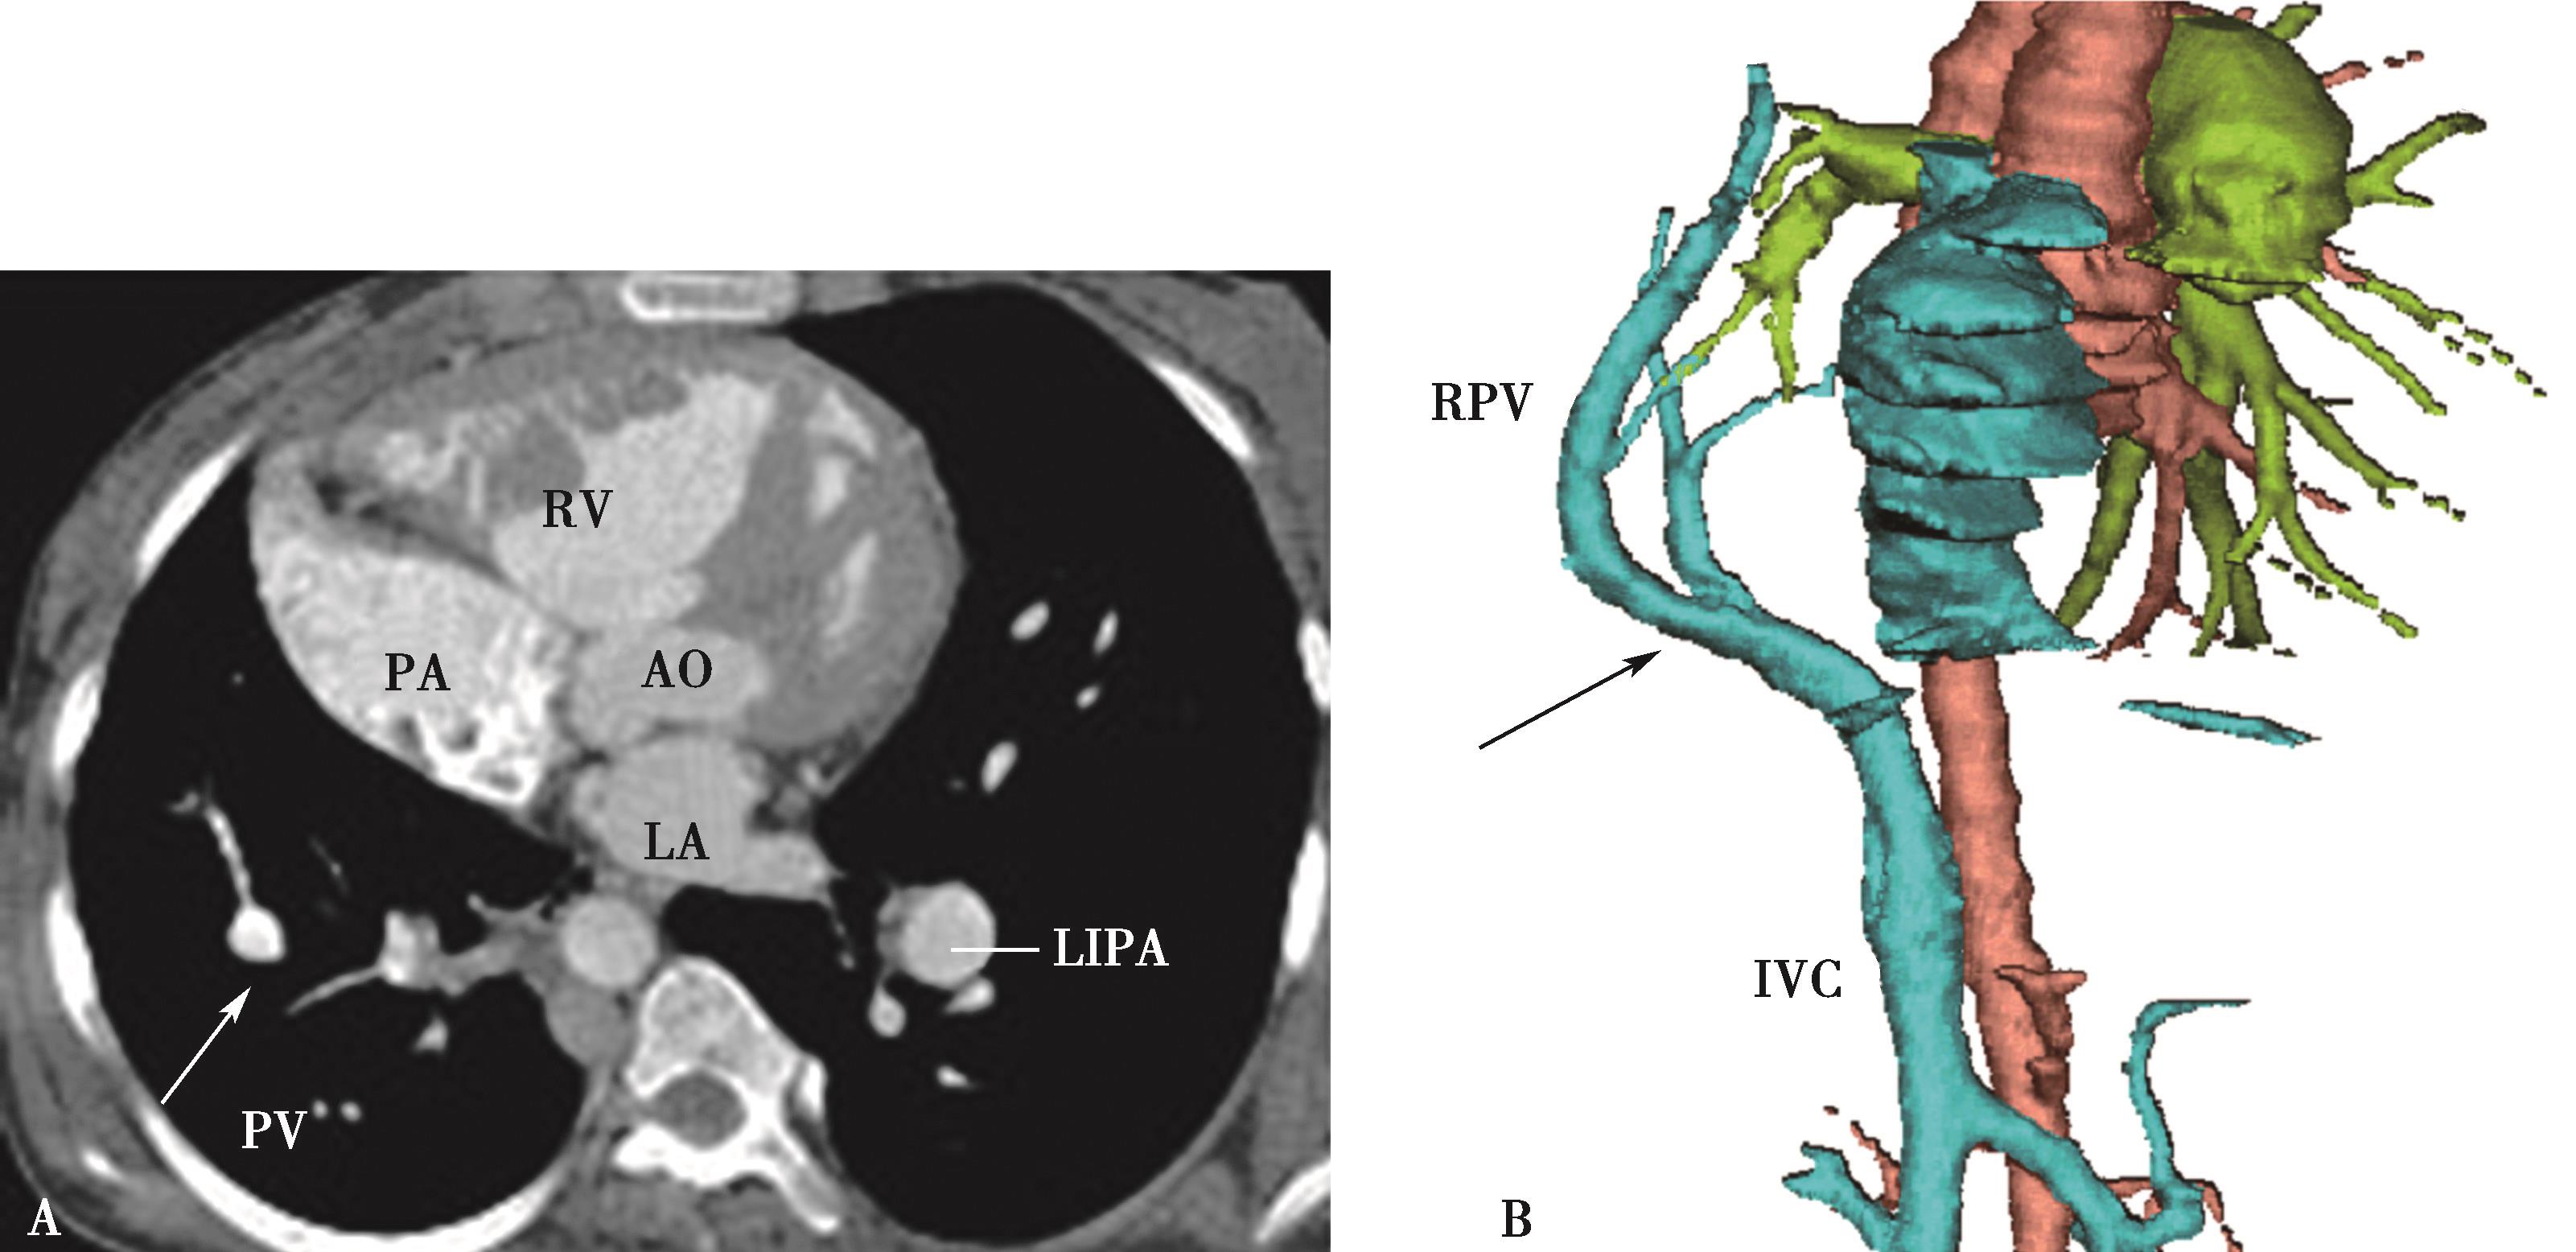

五、多排螺旋CT肺静脉造影方法

多排螺旋CT肺静脉造影检查多用于:①左心房-肺静脉检查,用以检查左心房,左心耳和肺静脉的解剖,评价肺静脉,评估左心房大小,检出左心房(耳部)血栓,指导临床诊断及射频消融治疗;②肺静脉疾患:肺静脉瘤,肺静脉狭窄,闭塞;回流异常等(包括先天性或获得性)。CT检查可以减少对有创检查的依赖、减少患者负担,有重大的优势。

(一)多排螺旋CT肺静脉造影检查方法

1.扫描的范围 从主动脉弓上水平到心脏膈面。

2.主要参数 以64排VCT为例,增强扫描参数设定为:电压120kV,电流400~600mA,机架转速0.35秒/圈,螺距为0.984∶1,准直器宽度为2.5mm,重建层厚0.625mm,视野(FOV)为25cm,矩阵512×512。由于采用的是智能监测跟踪技术。

3.扫描采用智能对比剂跟踪技术,监测层面设定在左心房的层面,ROI定为左心房,触发阈值定义为100~120HU。

4.对比剂 对比剂浓度320~370mgI/ml,采用单筒高压注射器团注,流率为4.0~5.0ml/s,对比剂总量为70~90ml。

5.一期扫描 当ROI的CT值达到阈值时启动增强扫描程序。第一期扫描得到完整的肺静脉-左心房图像。如果达到诊断目的,可结束扫描(图8-1-11)。

图8-1-11 肺静脉CTA检查

A.上肺静脉(↑);B.下肺静脉(↑);C.肺静脉最大密度投影。LSPV:左上肺静脉;LIPV:左下肺静脉;RSPV:右上肺静脉;RIPV:右下肺静脉